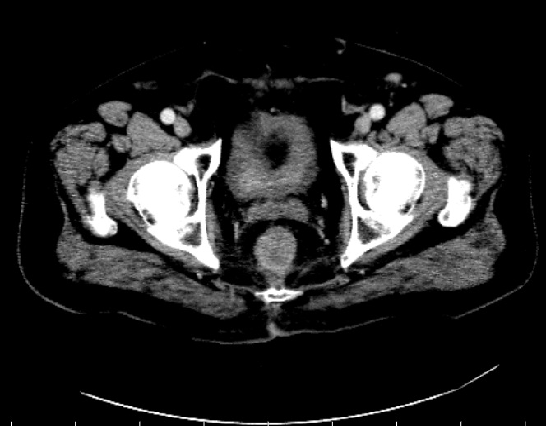

MR:1、直肠癌(T3可能),与右侧肛提肌关系密切,考虑1、炎性渗出粘连2、侵犯待排2、慢性膀胱炎3、前列腺增生。

2017-09 MR:

腹腔镜探查腹腔,见:肝脏表面,胰腺、腹腔、盆腔无肉眼可见转移结节,盆腔未见明显腹水。肿瘤位于直肠下段腹膜返折处,肿瘤侵及浆膜外,与周围组织粘连成团,冰冻骨盆。行乙状结肠造口术。

胸腹盆增强CT(2020-05-08):直肠癌治疗术后,左下腹造瘘术后,肝脏多发转移较前增多增大,双肺气肿,主动脉及冠状动脉硬化,双肾囊肿